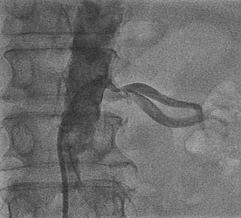

急性下壁心肌梗死(严重成角、巨大血栓病变)的急诊介入治疗

广西医科大学第一附属医院心内科、广西心血管病研究所术者:李浪助手:许春平 曾波病例描述:即往病史:黄XX,男,72岁,因持续剧烈胸